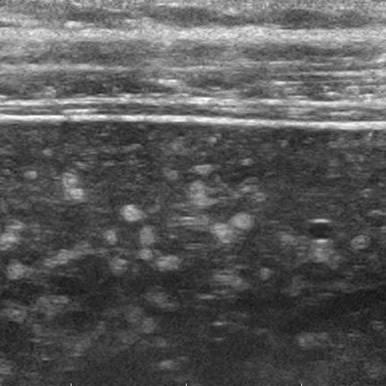

Hamartoma đường mật

» Thông tin: Nam giới – 34 tuổi.

» Lâm sàng: Kiểm tra sức khỏe.